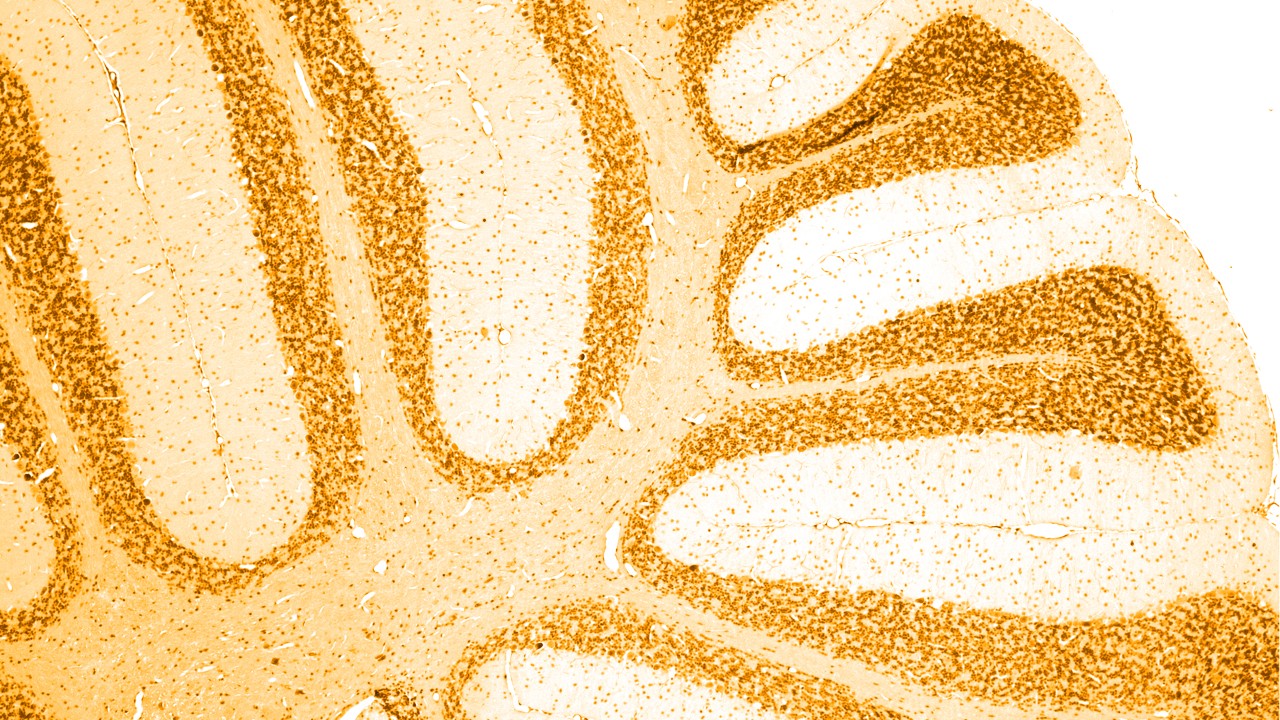

Neurologische Erkrankungen betreffen das zentrale und periphere Nervensystem und damit das Gehirn, das Rückenmark und alle Nerven und Muskeln, die die Körperfunktionen regulieren und koordinieren.

Es gibt viele verschiedene Ursachen für Demenz, von denen die häufigste die Alzheimer-Krankheit ist. Hier finden sich im Gehirn bestimmte Ablagerungen, sogenannte „Amyloid-Plaques“ und „Tau-Bündel“. Auch bei bestimmten anderen Demenzerkrankungen kommt es zu dieser nicht normalen Ansammlung von Tau-Proteinen im Gehirn; deshalb werden sie auch zusammenfassend als „Tauopathien“ bezeichnet.